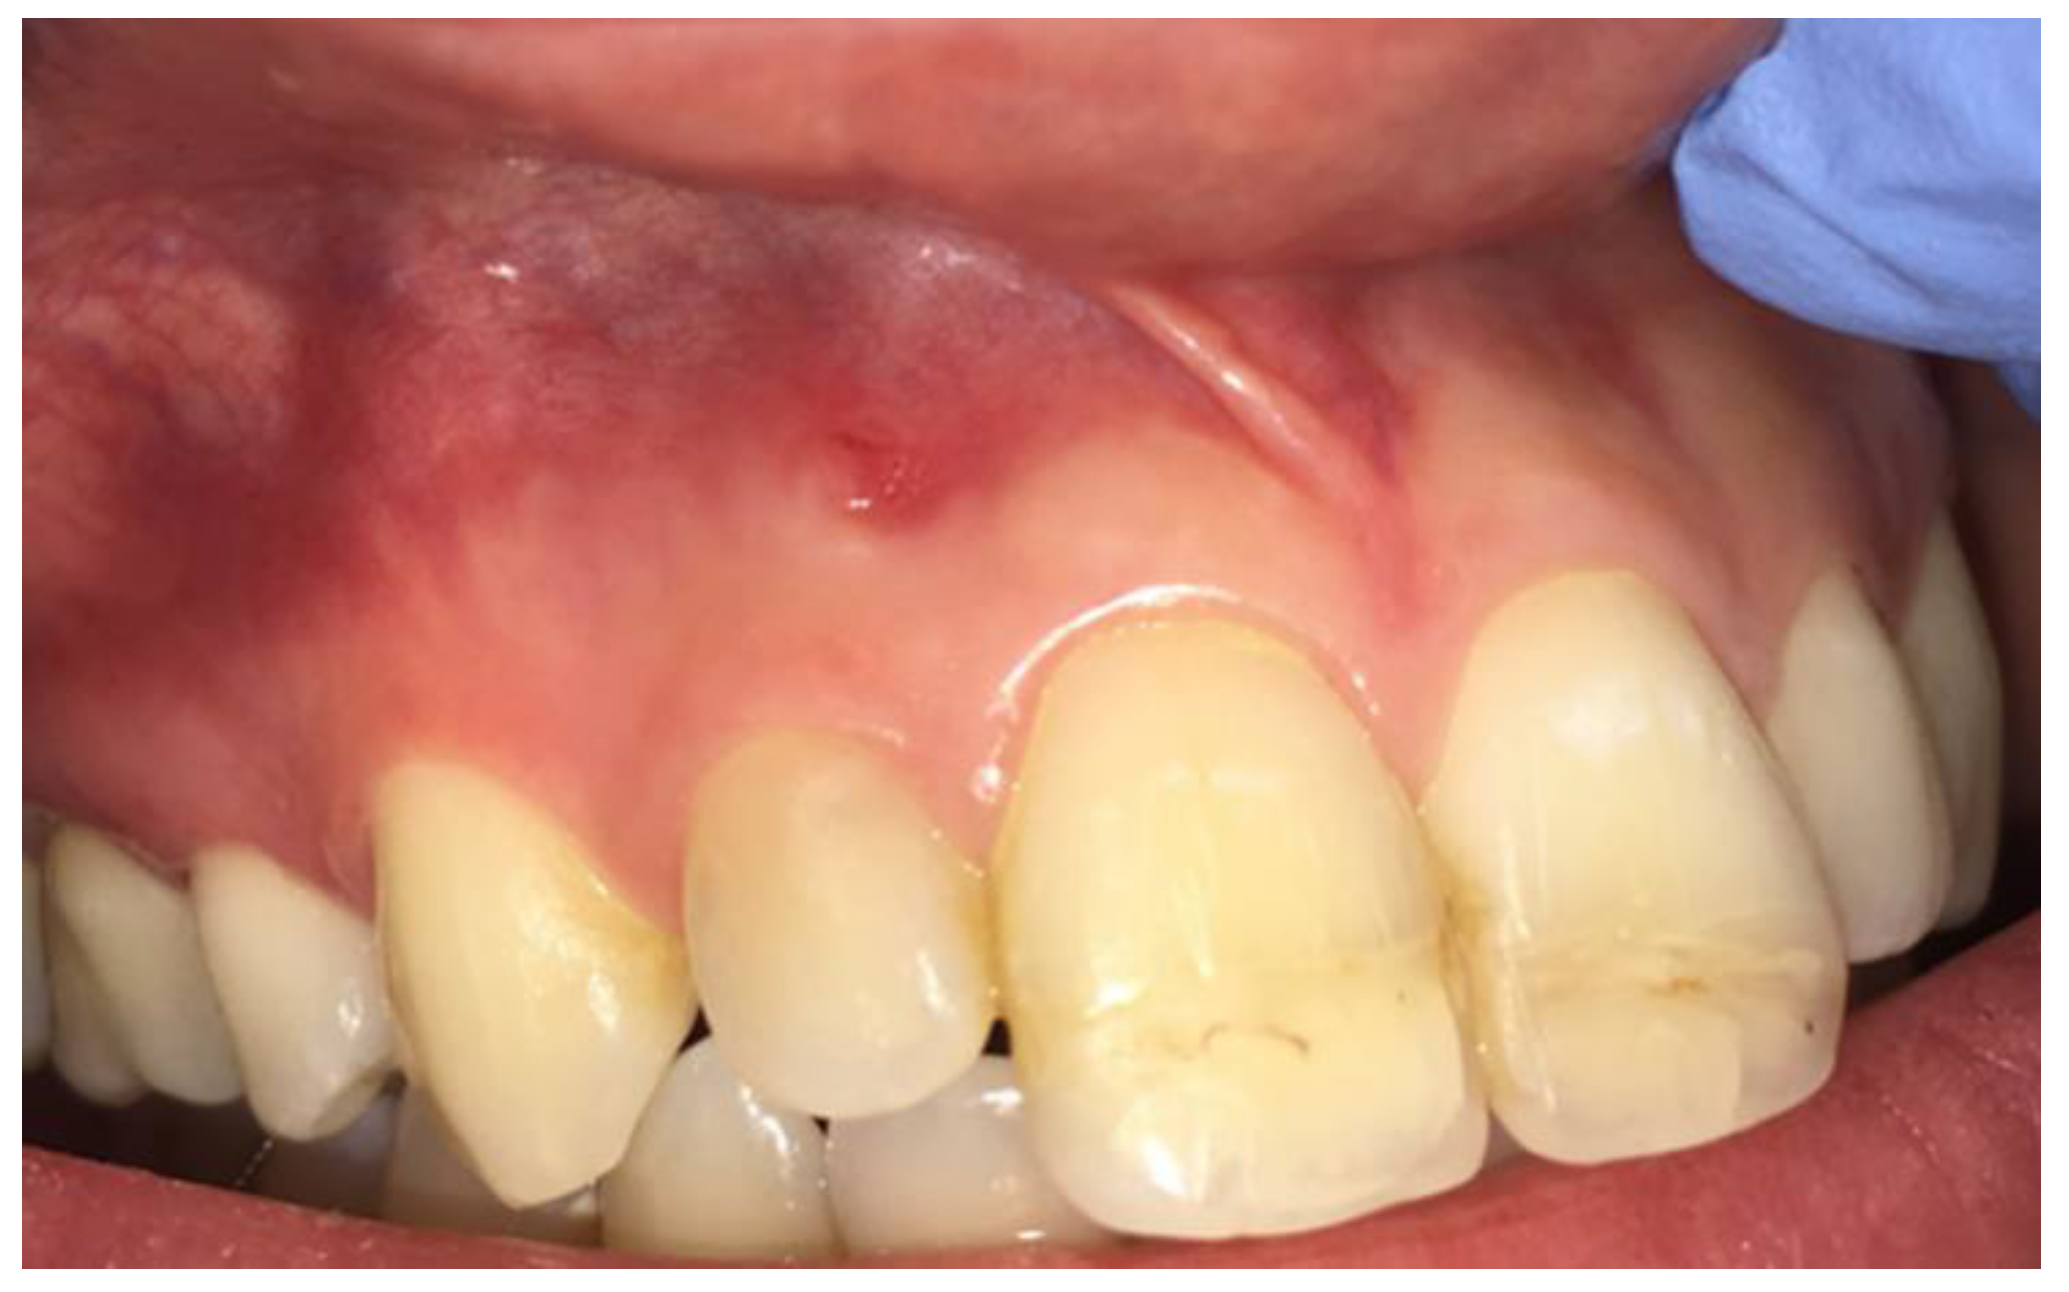

2. Case Report